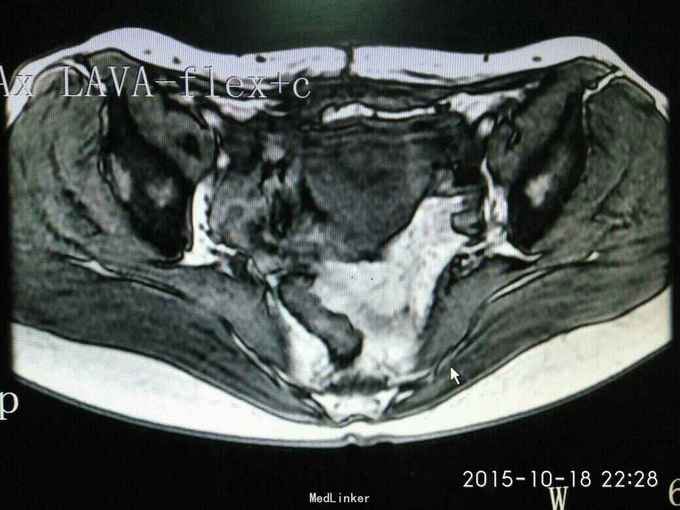

查体:妇检:外阴已婚已产式;阴道:畅,软,见少量淡黄色分泌物;宫颈少糜;子宫前位,鸭蛋大,无压痛;双侧附件未及异常。 辅助检查:我院病理会诊示:(子宫)低级别子宫内膜肉瘤。盆腔MRI示:子宫前壁近峡部肌层内异常信号。

诊断:子宫内膜间质肉瘤 治疗:全子宫+双侧附件切除术。术后病理报告示:(子宫)低级别子宫内膜间质肉瘤。宫旁、输卵管、卵巢未见癌组织累及。